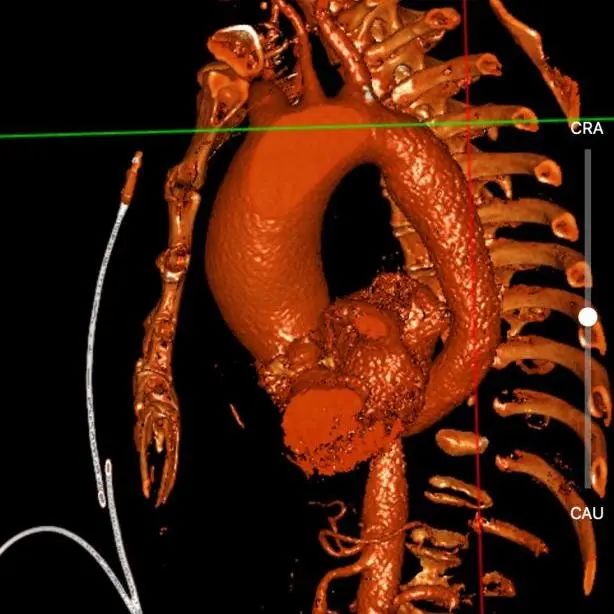

主动脉CT

瓣环85.7mm,平均径26.7mm,LOT周长88.5mm,平均径27.5mm,瓣叶L-R融合,瓣叶重度钙化,钙化主要分布于右瓣叶、无冠瓣和左右瓣叶融合脊,瓣上4/6mm,预计推开空间周长84.5mm。

冠脉风险高:左冠高度6.8mm,瓣叶10mm,左冠高风险,右冠风险可控。

升主动脉瘤样扩张,平均径57mm,且横位心71°,存在升主动脉破裂风险。

入路情况:胸主腹主动脉无明显迂曲,双侧股动脉入路较好,右股可作为主入路。